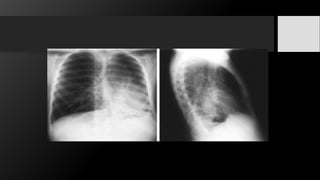

Radiografía

simple

• La radiografía PA de tórax revela un área de condensación unilateral con la presencia de

broncograma aéreo localizada en cualquier lóbulo; sin embargo, predomina en lóbulos

medio e inferior.

• Su apariencia es similar a la de cualquier proceso neumónico

Radiografía simple • La radiografíaPA de tórax revela un área de condensación unilateral con la presencia de broncograma aéreo localizada en cualquier lóbulo; sin embargo, predomina en lóbulos medio e inferior. • Su apariencia es similar a la de cualquier proceso neumónico TC • Se identifica la zona de condensación con broncograma aéreo y la adenopatía de manera característica presenta áreas de baja atenuación secundaria a necrosis con la presencia de captación anular del contraste y obliteración de la grasa perinodal. Gammagrafía con citrato de gallium-67. • Los leucocitos autólogos marcados con indium 111 y la TEP con FDG son de utilidad en el paciente con fiebre de origen desconocido y en el que no se ha identificado una fuente definitiva con otras modalidades de imagen.